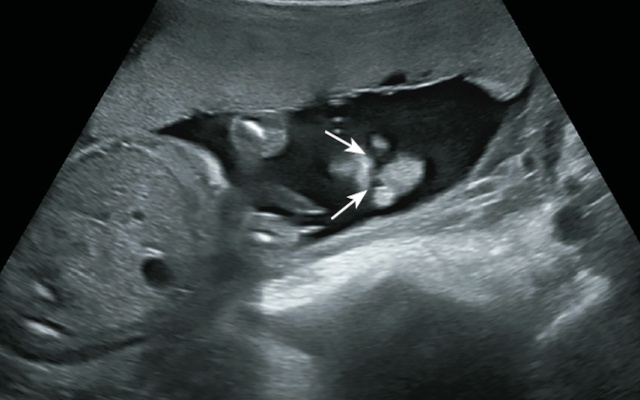

На рис. 4-6 представлены изображения двусторонней расщелины губы и нёба у плода женского пола в 20-21 нед беременности. Ширина дефектов составляет 3,9 и 1,7 мм.

Рис. 4. Двусторонняя расщелина губы и нёба (стрелки) - 21 нед беременности.

Рис. 5. Двусторонняя полная расщелина (стрелки).